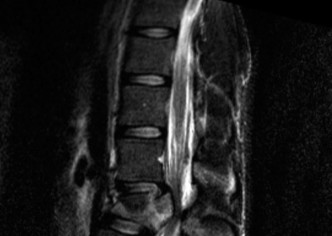

The options for definitive treatment of cervical facet dislocations? CASE 24 A 23-year-old man presents to your emergency room with severe back pain after a 30-foot fall out of a tree while intoxicated 3 hours earlier. He reports no neck pain, no upper extremity weakness or numbness, though he states that he feels weak in his legs and numbness in his groin. Currently, he is awake, alert, oriented, and cooperative and does not appear to be intoxicated. Vital signs included a blood pressure of 100/60 and heart rate of 95 beats per minute. Physical examination demonstrates midline tenderness of the lumbar spine with no palpable gap or step-off. Upper extremities show full strength and sensation. Lower extremities examination shows 2/5 bilateral strength in hip flexion and knee extension, 3/5 bilateral strength of ankle dorsiflexion, big toe extension, and ankle plantar flexion. Rectal tone is normal. Sensation to light touch and pin prick is diffusively decreased in both lower extremities and in the perineum. Bulbocavernosus reflex is present. A CT scan of his cervical and thoracic spine is negative. CT images of his lumbar spine are shown in Figures 1–32 and 1–33.

Figure 1–32

Figure 1–33

The injury of L2 is best described as which of the following?

Discussion

The correct answer is (B). The CT images reveal a comminuted fracture of the L2 vertebral body with involvement of its posterior aspect. The distinguishing feature between a burst fracture and a compression fracture is involvement of the posterior aspect of the vertebral body. Furthermore, burst fractures demonstrate that the posterior body fragments are no longer in continuity with the posterior elements (i.e., pedicles). Thus, they are free fragments that often are retropulsed into the spinal canal. Lamina fractures are often concomitant at the level of a burst fracture. By themselves, they do not infer injury to the posterior ligamentous complex. They can, however, be associated with dural tears and nerve root entrapment. Flexion–distraction injuries, also known as Chance or seat belt injuries, demonstrate widening of the posterior elements, either between the spinous processes, gapping at the facet joints, or through fractures in the posterior elements. There can be varying degrees of vertebral body compression, though typically not with comminution of the posterior vertebral margin. Fracture-dislocations can present with various

fractures of the anterior or posterior elements. The hallmark feature is a translation deformity that can be noted by misalignment of the vertebral bodies in the coronal and/or sagittal planes. A lumbar spine MRI is obtained, images from which are shown inFigures 1–34 and 1–35. Based on the information presented, the type of neurological injury is best characterized as which of the following? 1. Cauda equina injury

Figure 1–34

Figure 1–35

The correct answer is (A). The MRI demonstrates the L2 fracture with canal compromise. In this patient, the conus medullaris of the spinal cord terminates at the T12–L1 level. The fracture is at the L2 level. Thus, the neurological injury is at the level of the cauda equina, distal to the conus medullaris and spinal cord. The patient’s neurological examination is consistent with this type of injury with the presence of lower extremity weakness, intact rectal tone, and perineal numbness, though this can vary.